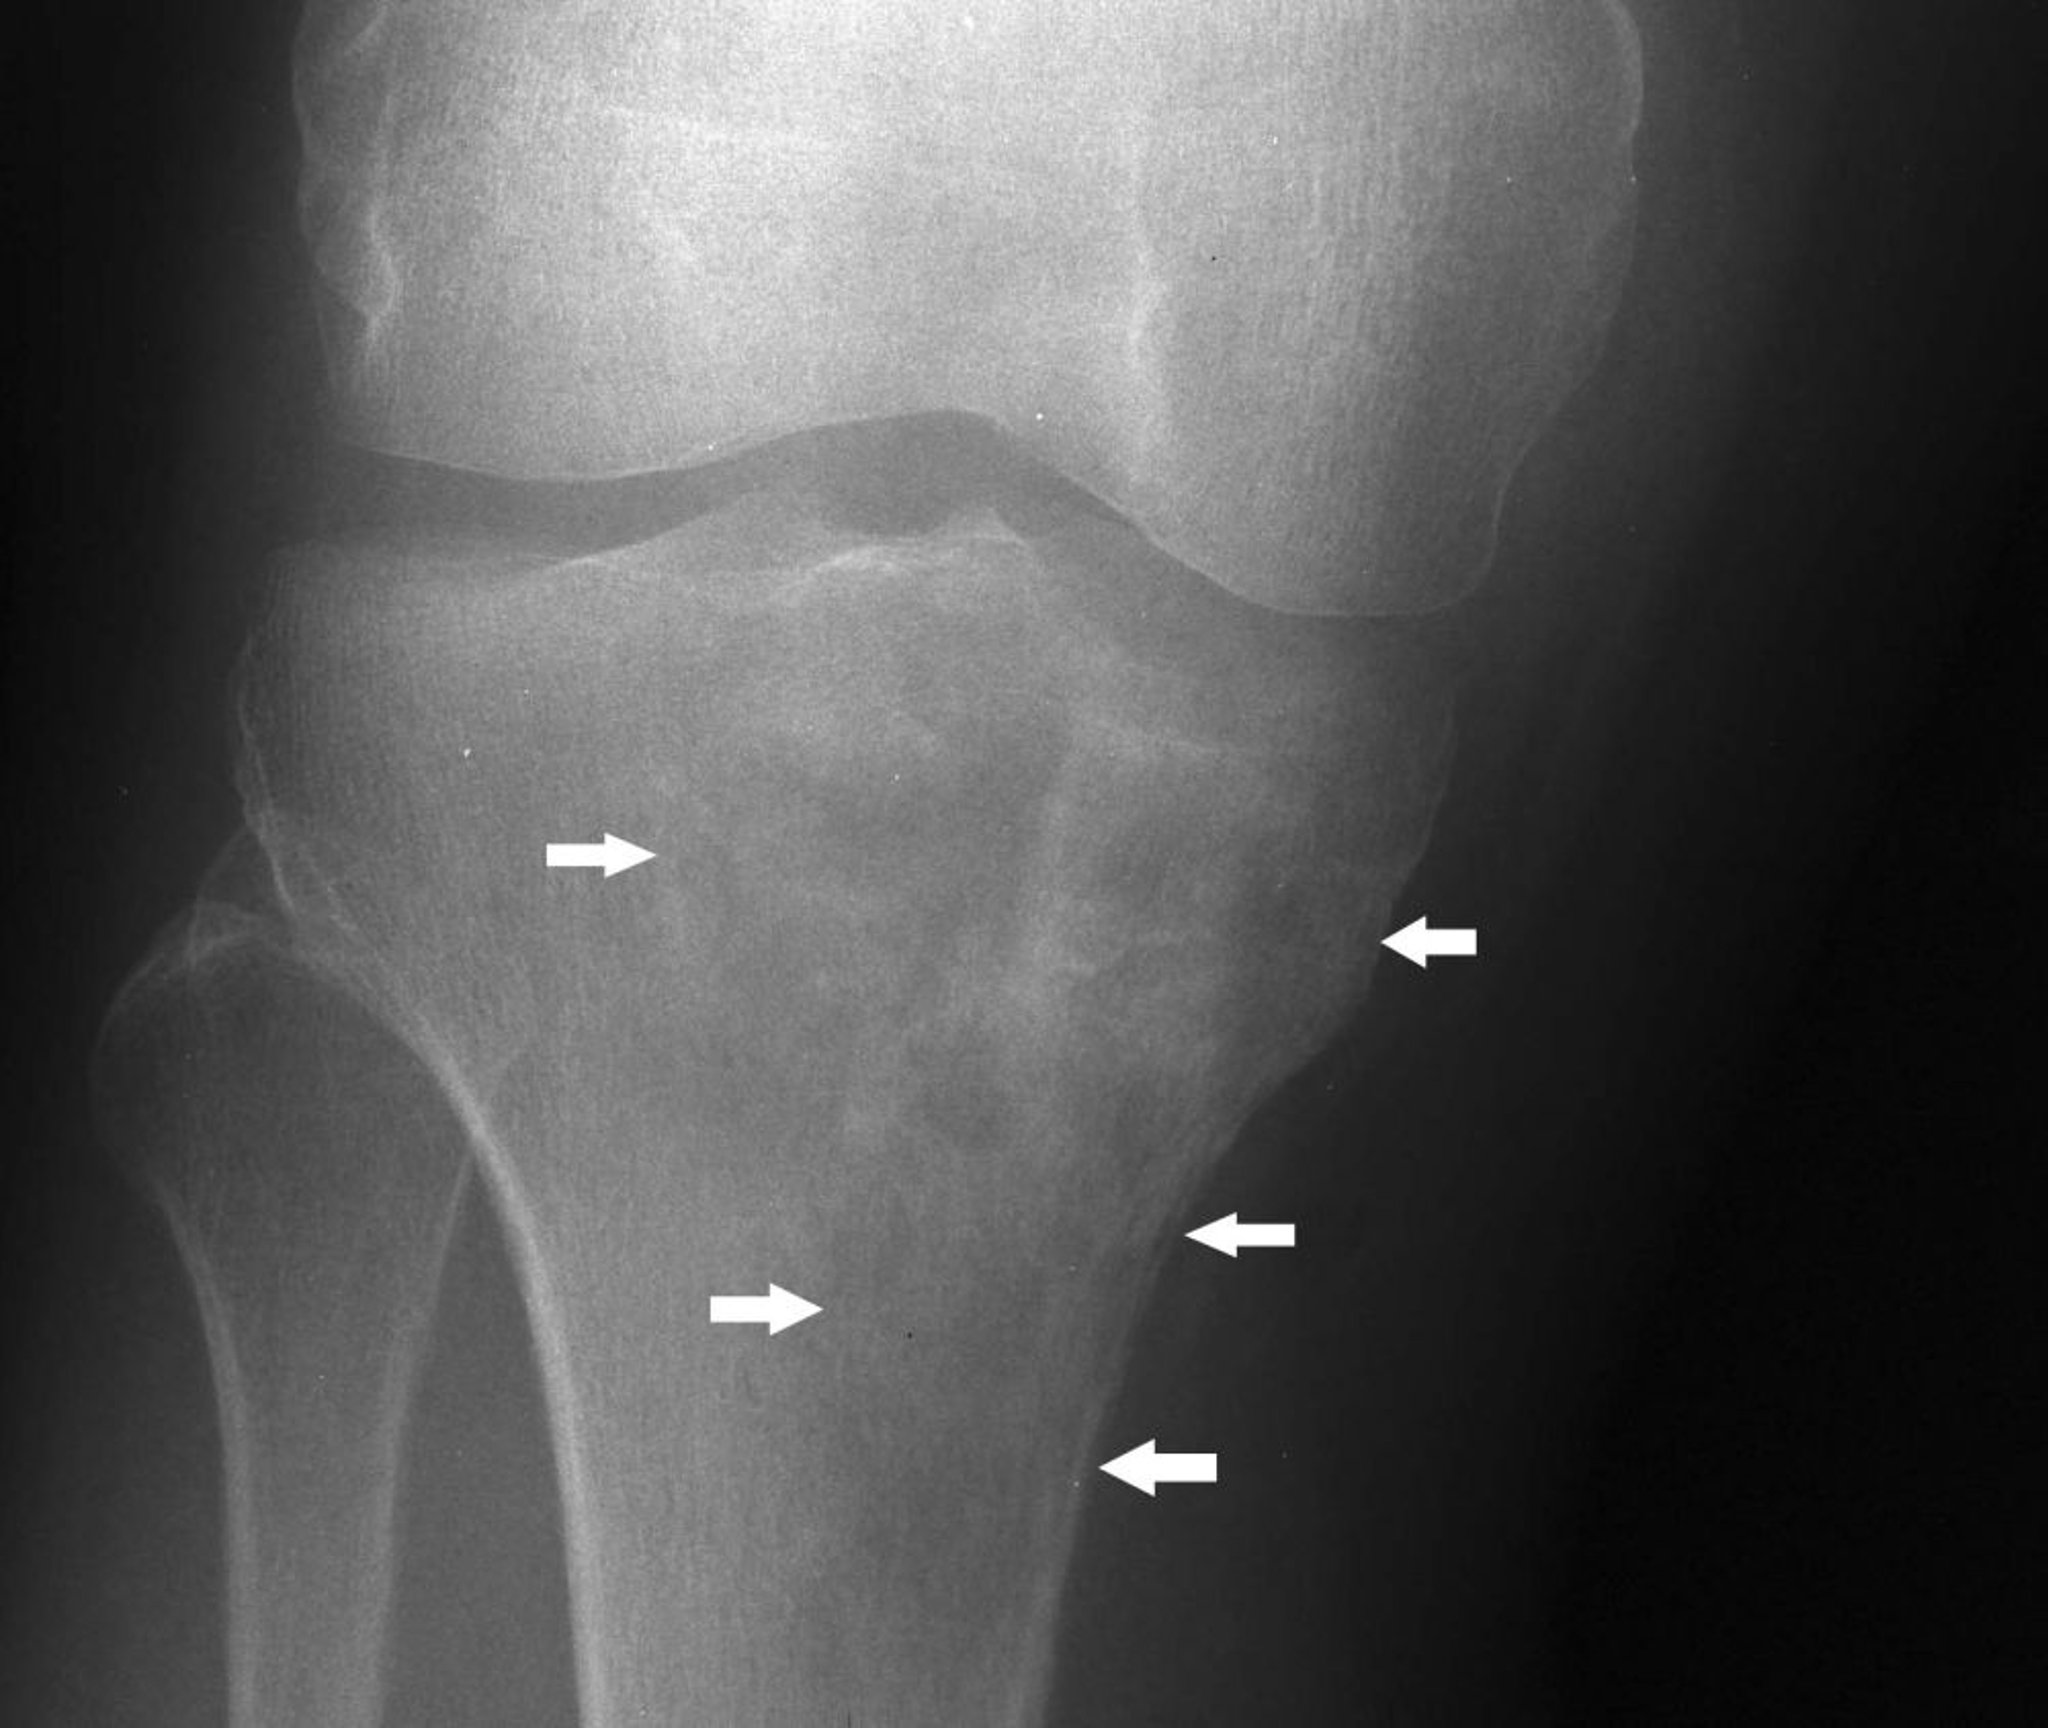

На данном рентгеновском снимке колена показана лимфома в проксимальной части большеберцовой кости со смешанным литическим и склеротическим проявлением ниже медиального мыщелка большеберцовой кости (стрелки).

Image courtesy of Michael J. Joyce, MD, and Hakan Ilaslan, MD.